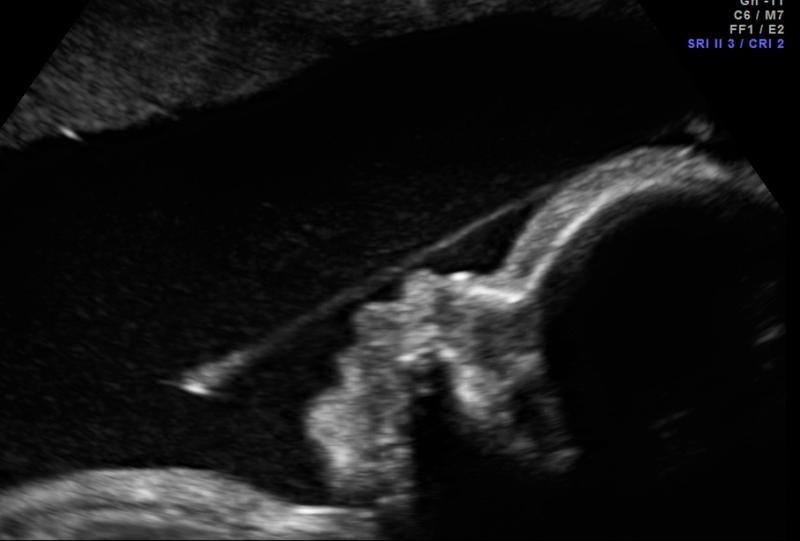

Diagnostyka zespołu pasm owodniowych wymaga nowoczesnych technik obrazowania, głównie ultrasonografii. Subtelność objawów powoduje trudności w rozpoznaniu, zwłaszcza na starszym sprzęcie. Regularne badania kontrolne oraz wykorzystanie specjalistycznego sprzętu są niezwykle ważne do wykrycia ewentualnych nieprawidłowości w odpowiednim czasie.

Metody diagnostyczne oceniające stan taśmy owodniowej są kluczowe dla zdrowia matki i płodu. Nowoczesne techniki obrazowania umożliwiają lekarzom identyfikację problemów przed ich rozwojem w poważne zagrożenia. Ultrasonografia wizualizuje struktury wewnątrzmaciczne oraz wykrywa nieprawidłowości naczyniowe.

Ultrasonografia określa, czy naczynia płodu znajdują się w pępowinie, czy w błonach owodniowych. Postawienie diagnozy wymaga dużego doświadczenia specjalisty, dlatego lekarze mogą zaproponować dodatkowe procedury, takie jak rezonans magnetyczny, który dostarcza szczegółowych obrazów zdrowia płodu.

Diagnostyka taśmy owodniowej opiera się głównie na zaawansowanych technikach obrazowania, takich jak ultrasonografia, co pozwala na wykrywanie nieprawidłowości w ułożeniu naczyń krwionośnych. Specjaliści mogą podejmować odpowiednie działania terapeutyczne. W trudnych przypadkach lekarze mogą zlecić inwazyjne badania, na przykład amniocentezę.